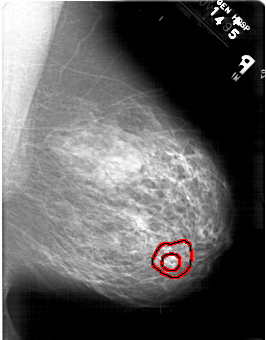

A_1467_1.RIGHT_MLO

RIGHT_MLO LINES 6106 PIXELS_PER_LINE 4771 BITS_PER_PIXEL 12 RESOLUTION 43.5 OVERLAY

FILE: A_1467_1.RIGHT_MLO.OVERLAY

TOTAL_ABNORMALITIES 1

ABNORMALITY 1

LESION_TYPE MASS SHAPE ARCHITECTURAL_DISTORTION MARGINS SPICULATED

ASSESSMENT 5

SUBTLETY 1

PATHOLOGY MALIGNANT

TOTAL_OUTLINES 2

BOUNDARY

CORE